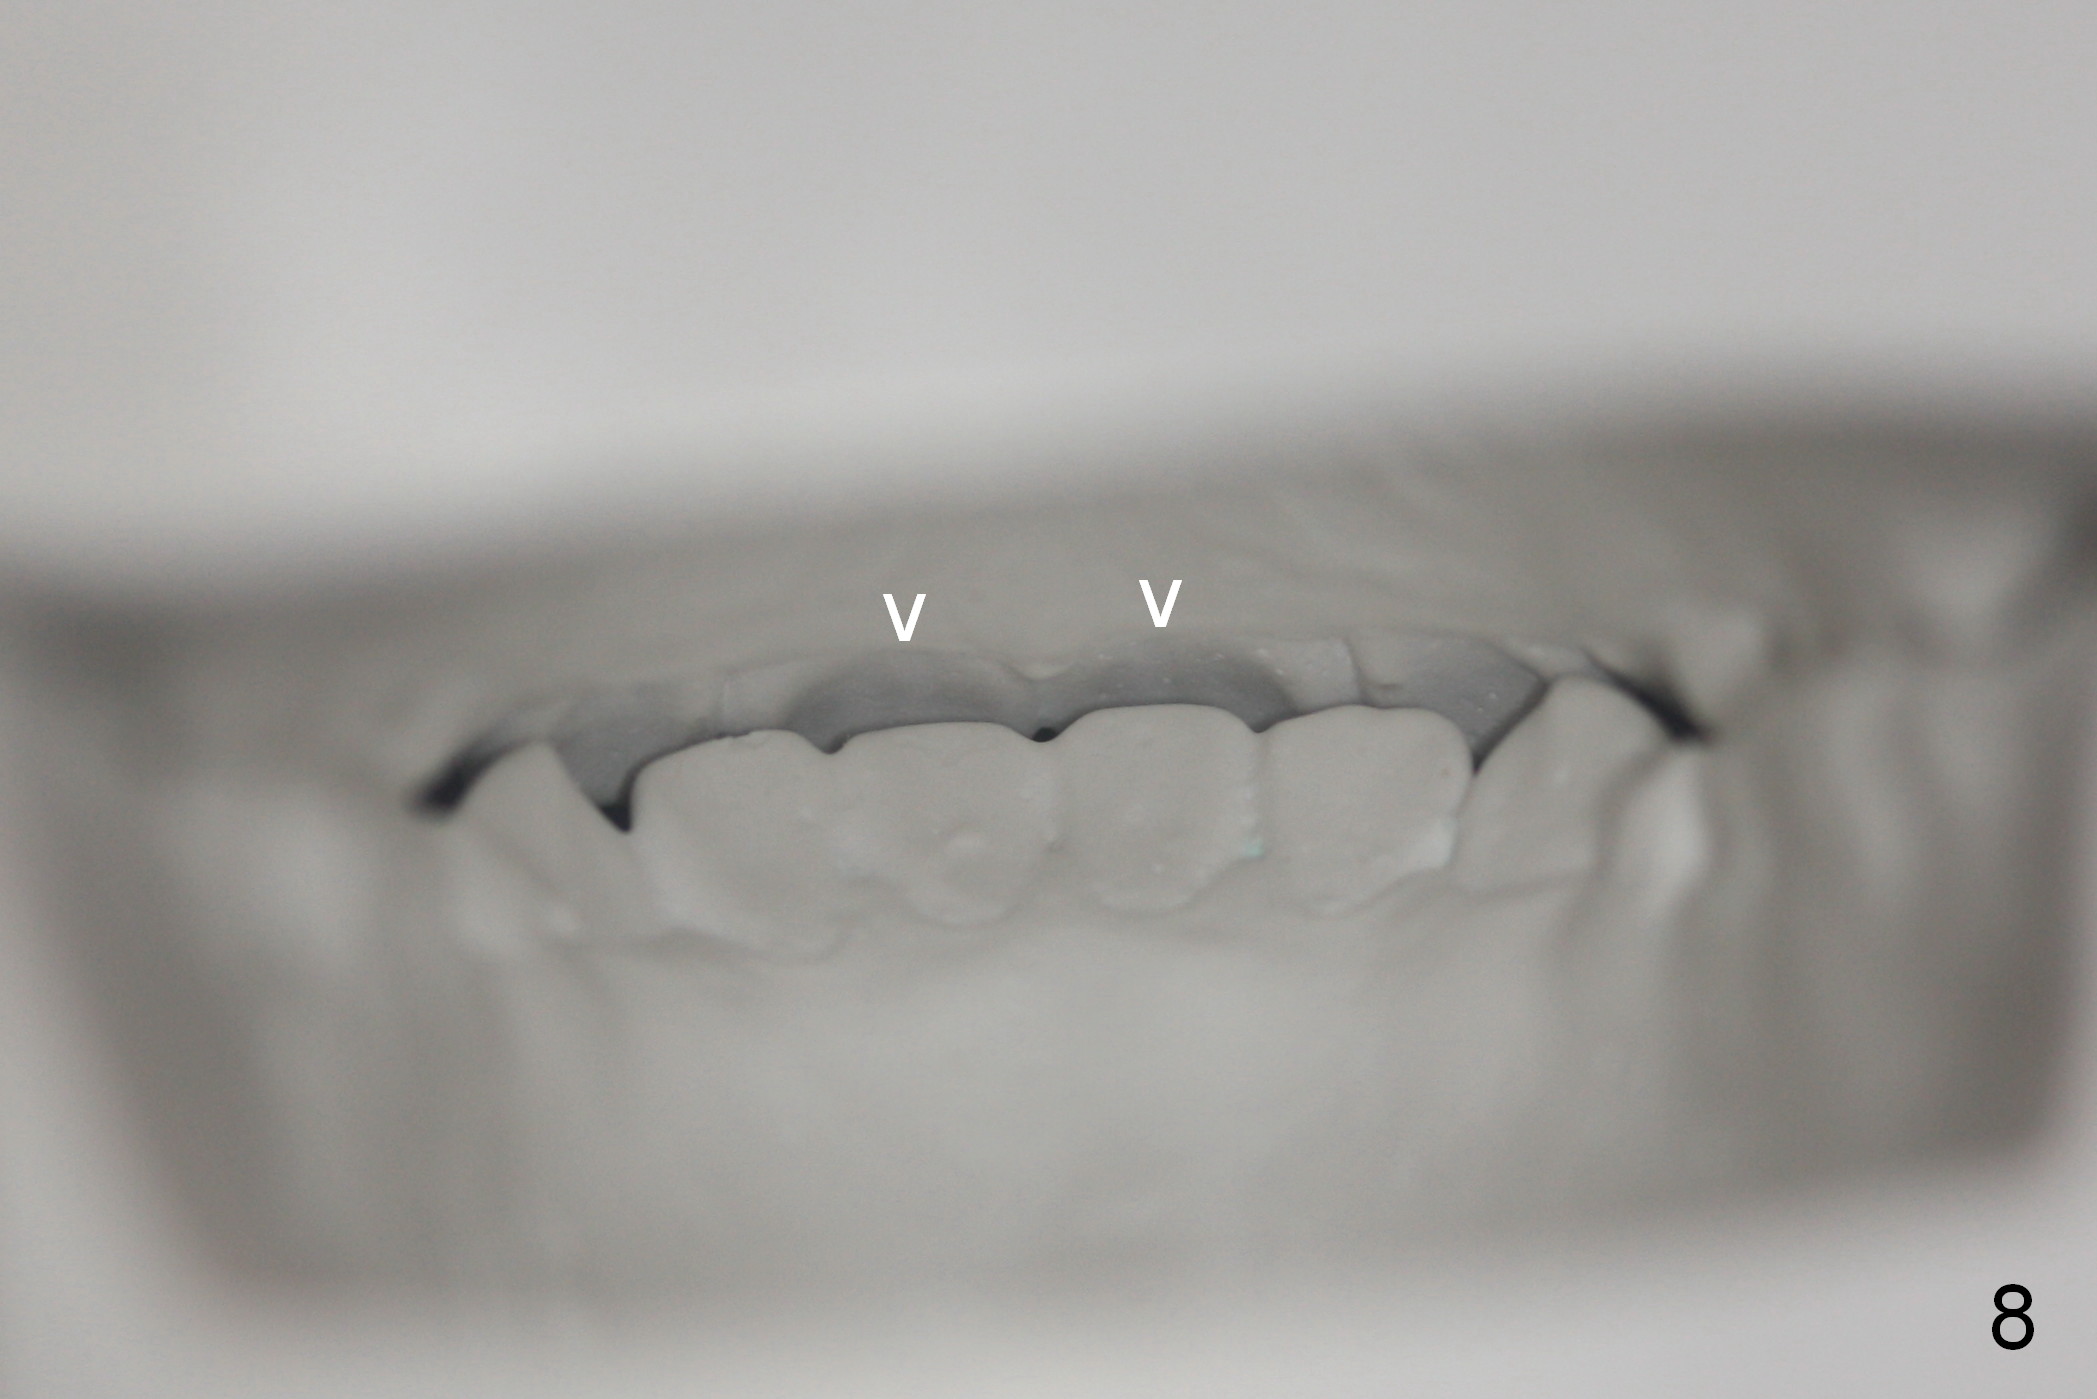

Joshua, 11 years old, has dental crowding (Fig.1), particularly in the lower arch (Fig.3) with molar Class I relationship (Fig.2). The lower 5s rotate (Fig.2 black lines), which are corrected with power chains (Fig.4,5) after bracketing and placing .012" niti wires (Fig.6).

The orthodontic treatment finishes in 9 months. Incisor overbite improves (compare Fig.7,8 (lingual view of the anterior arches; arrowheads: upper palatal gingival margin)). The rotation of the lower 2nd bicuspids (Fig.9 black lines, as compared to those in Fig.3) and the crowding of the lower anterior teeth (Fig.9) also improves. Two years later, the latter relapses.